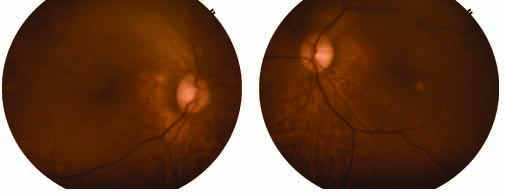

What does Fundus Photography do?

- Fundus Photography for 5 clinical disease which cause most

cases of preventable blindness.

1-Diabetic Retinopathy

2-Age Related Macular Degeneration

3-Glucoma

4-Hypertensive Retinopathy

5-Cataract